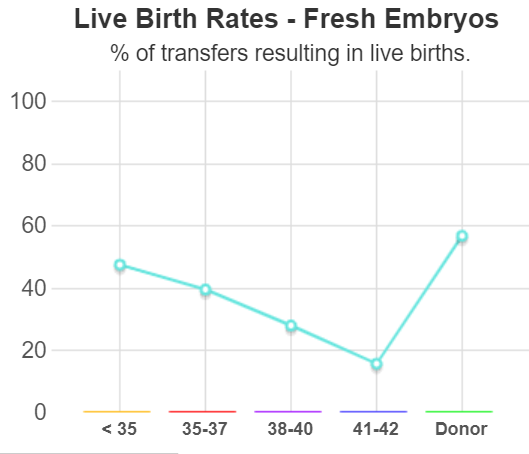

试管婴儿技术在过去的几十年里发生了很多变化,期间,研究者一直致力于降低多胎妊娠的发生率。研究者普遍将多胎妊娠看做是试管婴儿技术中最严重的并发症之一。一些欧洲国家强...

试管婴儿正迅速成为世界上最常用的生育治疗方法。IVF是用于诊断不育的经典原因还是用于冷冻卵子,对胚胎进行基因筛查,或者为将来使用储存胚胎,IVF提供了许多优于传统...

随着试管婴儿技术和胚胎冷冻技术的发展,越来越多的医生和]患者选择冷冻胚胎移植来助孕。因为冷冻胚胎移植与新鲜胚胎移植相比较,女性体内激素水平更加接近自然,内膜的处理...